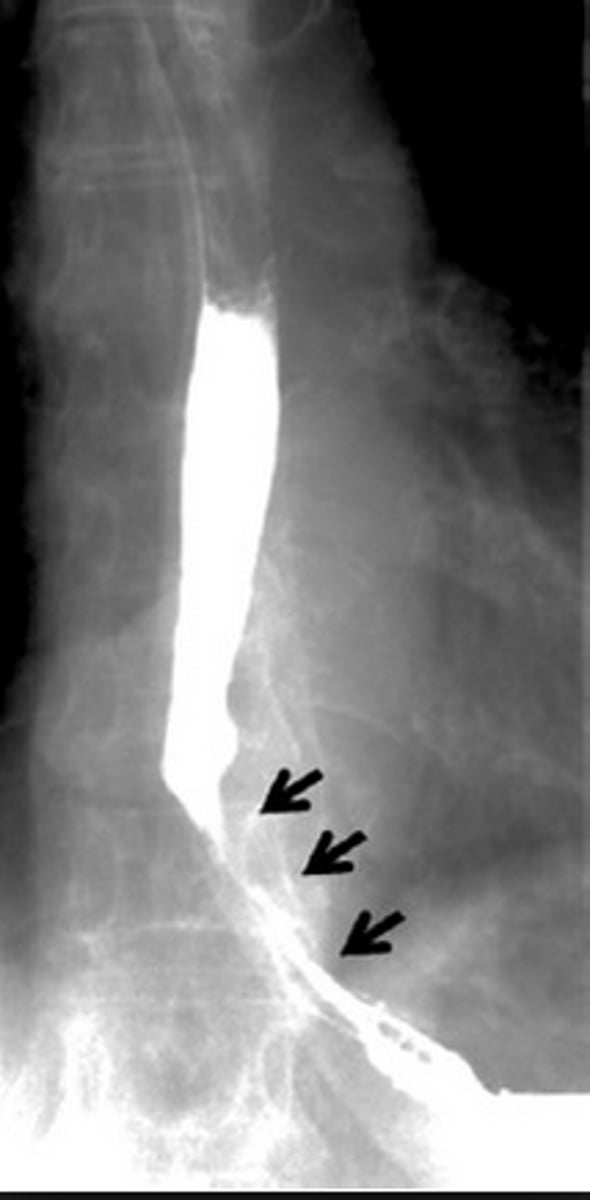

esophagus

best assessed by upper endoscopy, barium swallow, or gastrofin swallow

Z line- sometimes visible, junction between mucosa of esophagus and stomach

Zenker diverticulum

abnormal "pouch", food can get caught causing dysphagia

esophageal strictures

narrowing of the esophagus

superior- scarring from suicide attempts, lye or corrosive material swallowed, smooth appearance

middle and inferior- scarring from GERD, neoplasm

esophageal carcinoma

irregular column of barium entering stomach with peak like projections of barium -> concerning for malignancy